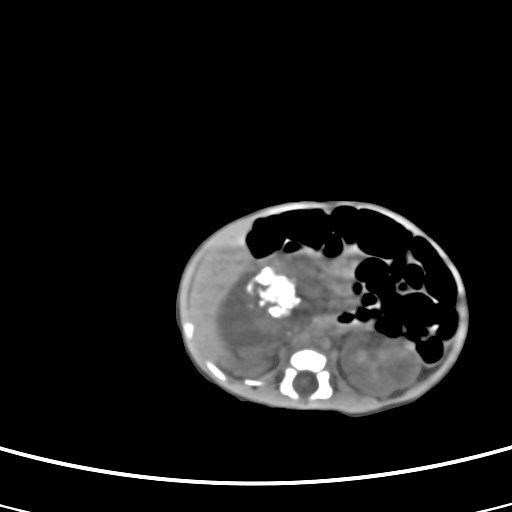

患儿,男性,出生后2天,在胎儿时b超已发现病变,患儿一般情况可。因病变部位偏向于右侧肾上腺区,目前考虑为神经母细胞瘤,不知各位能否支持。

病灶内未见明显脂肪密度。

反对定位在右肾上腺区的说法,那么神经母细胞瘤也可以暂时不予考虑。请看下图:

下面这幅图中,似乎可以见到肿瘤的薄包膜,其后与右肾之间的又是什么东西呢?这关系到肿瘤的定位、定性。我考虑病灶是位于肝十二指肠韧带内的畸胎瘤可能性比较大。请各位老师仔细看一下:

病灶巨大,位于右侧肾上腺区,与周围组织分界欠清,内见不规则钙化影,无明显脂肪组织,首先考虑神经母细胞瘤,但畸胎瘤不能排除。

支持守望可可西里分析。下腔静脉的位置很关键。

手术结果为畸胎瘤